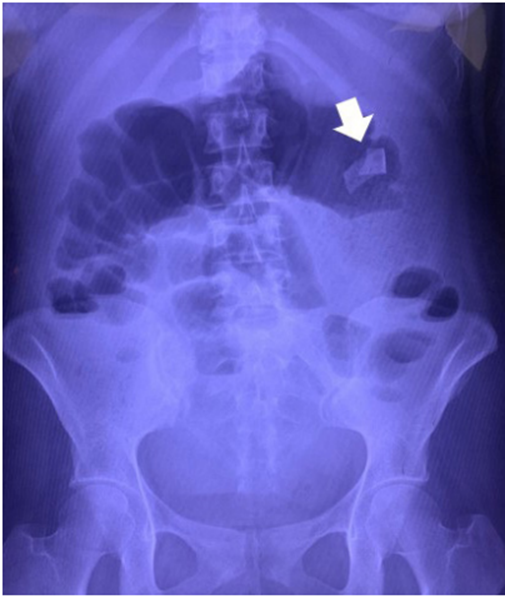

Paciente femenina de 24 años, con antecedente de una cesárea tipo Kerr cuatro meses previos, quien acude al servicio de urgencias refiriendo cuadro de un mes de evolución con dolor abdominal difuso, náuseas, vómitos y constipación intestinal. Al examen físico se encontró una masa móvil en el cuadrante superior izquierdo del abdomen. Se realizó radiografía de abdomen donde observan probable cinta radiopaca de textil quirúrgico (figura 1).

Figura 1. Radiografía de abdomen donde se aprecia cinta radiopaca de compresa quirúrgica (flecha blanca).